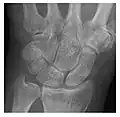

Figure 3: A 26-year-old man presenting with wrist pain after being assaulted. (a) Initial anteroposterior radiograph shows a subtle linear lucency within the scaphoid extending to the scaphocapitate articular surface that was overlooked (arrow). (b) Initial "scaphoid" view was negative. (c) Followup anteroposterior radiographs, 12 days later, shows obvious scaphoid fracture (arrows).[1]

The general rule is to perform two orthogonal views, but more specific views should be added if there is any suspicion of fracture. Moreover, one should be aware of the commonly encountered lesions and their locations. In wrist trauma, for instance, the interpreter should pay close attention to the scaphoid and triquetrum, which are the two most commonly injured carpal bones. The mechanism of trauma may also be helpful to locate the potential fracture. A fall on an outstretched hand suggests scaphoid fracture. Although the classical presentation consists of a radiolucent line and cortical disruption, the radiographic signs will depend upon the time elapsed between the first clinical symptoms and the time of radiographic examination, the location of the fracture within the bone, and the ratio of cortical to cancellous bone. Particular attention should be paid when analysing the subchondral plate, which may be disrupted or deformed. In metaphyseal areas, delayed signs of fracture include a band of sclerosis perpendicular to the trabeculae, while diaphyseal fractures may present as periosteal thickening.[1]

Occult osseous injuries may result from a direct blow to the bone by compressive forces of adjacent bones against one another or by traction forces during an avulsion injury. Lesions in the tibial plateau, hip, ankle, and wrist are often missed. In a tibial plateau fracture, any disruption of the posterior and anterior cortical rims of the plateau should be sought. Impaction of subchondral bone will appear as an increased sclerosis of the subchondral bone (Figure 1). In the hip, posterior acetabular fractures also present subtle radiographic findings. The acetabular lines should then be carefully examined keeping in mind that the posterior rim, which is harder to see on X-rays, is more frequently fractured than the anterior rim (Figure 2). In the wrist, detection of carpal bone fractures is often challenging, with up to 18% of scaphoid fractures radiographically occult. Carpal fractures, especially the scaphoid, are associated with the risk of avascular necrosis. In apparently normal wrist radiographs from symptomatic patients, if there is history of a fall on an outstretched hand with pain in the anatomic snuffbox, suggesting scaphoid injury, the initial examination with posteroanterior, lateral, and pronation oblique views must be complemented by other specific views such as supination oblique and the "scaphoid" view A careful examination of cortices for evidence of discontinuity or offset and cancellous bone for lucency is necessary (Figure 3).[1]